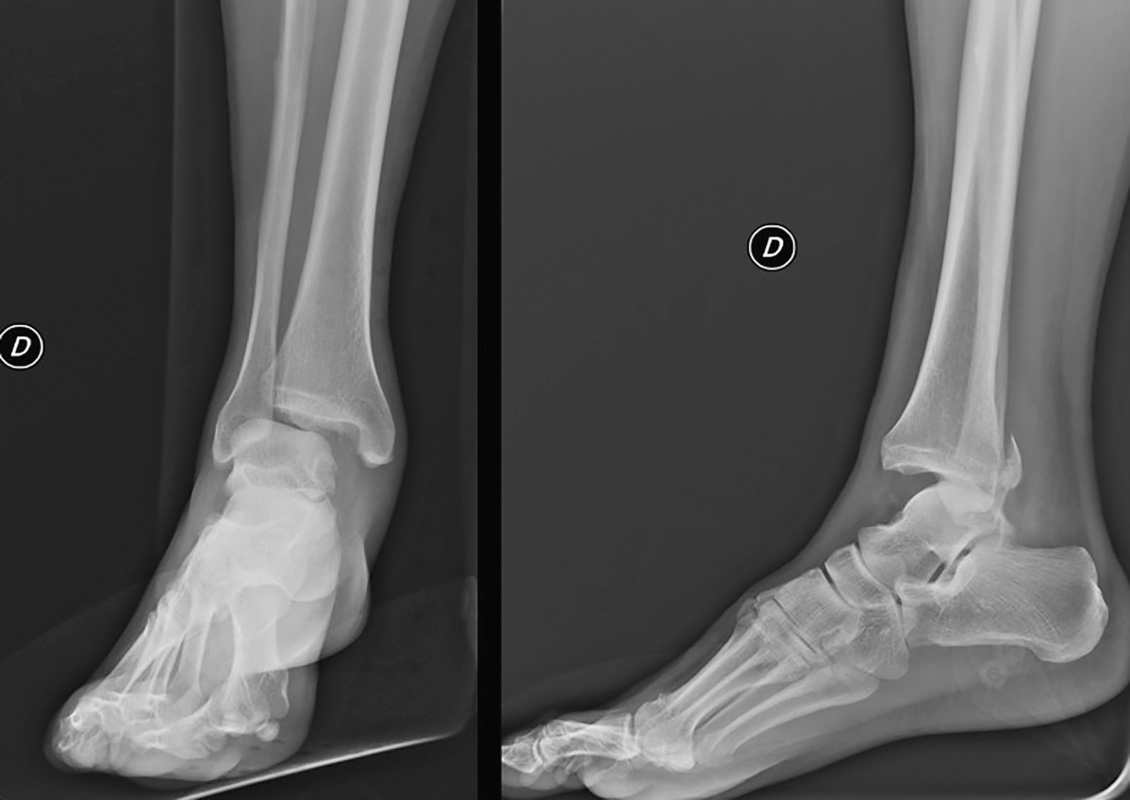

Le fratture malleolari sono fratture articolari causate da trauma diretto o più frequentemente, soprattutto in quelle da fragilità, da trauma indiretto di traslazione o di rotazione. Tali forze possono provocare anche una sublussazione oppure una lussazione dell’astragalo che non trova più la propria congruità all’interno del mortaio tibio-tarsico (Fig. 1). La posizione del piede e la direzione della forza deformante sono elementi fondamentali per capire il tipo di lesione. Proprio sulla base del meccanismo traumatico sono state ideate diverse classificazioni1-3. Le fratture malleolari possono coinvolgere solo il malleolo peroneale o quello tibiale (fratture monomalleolari), entrambi (fratture bimalleolari), oppure contestualmente anche il margine posteriore del pilone tibiale detto “terzo malleolo” (fratture trimalleolari).

La lesione trans-sindesmosica (Tipo B) si verifica a causa di un carico assiale sul piede supinato; l’inversione provoca la rotazione esterna dell’astragalo. In primis si ha una frattura obliqua di perone (Fig. 2) e la progressiva rotazione esterna dell’astragalo può provocare una scomposizione posteriore con lesione del legamento posteriore della sindesmosi o frattura del terzo malleolo. Infine, mentre l’astragalo si sublussa posteriormente, il compartimento mediale della caviglia cede o per una rottura del legamento deltoideo o per una frattura trasversa del malleolo mediale.